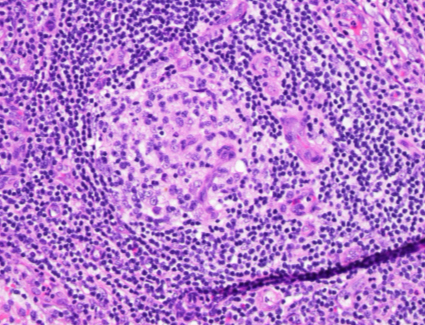

H&E (400x magnification)

The low power view shows lymph node tissue with abnormal follicles, including partial hyalinization, regression of germinal centers, and concentric mantle zone lymphocytes showing "onion skinning" appearance. Several follicles show prominent penetrating venules. No Hodgkin-Reed-Sternberg cells or LP cells were identified.

Immunohistochemical staining shows a polytypic plasmacytosis with no increase in IgG4+ plasma cells. HHV8 staining is negative.